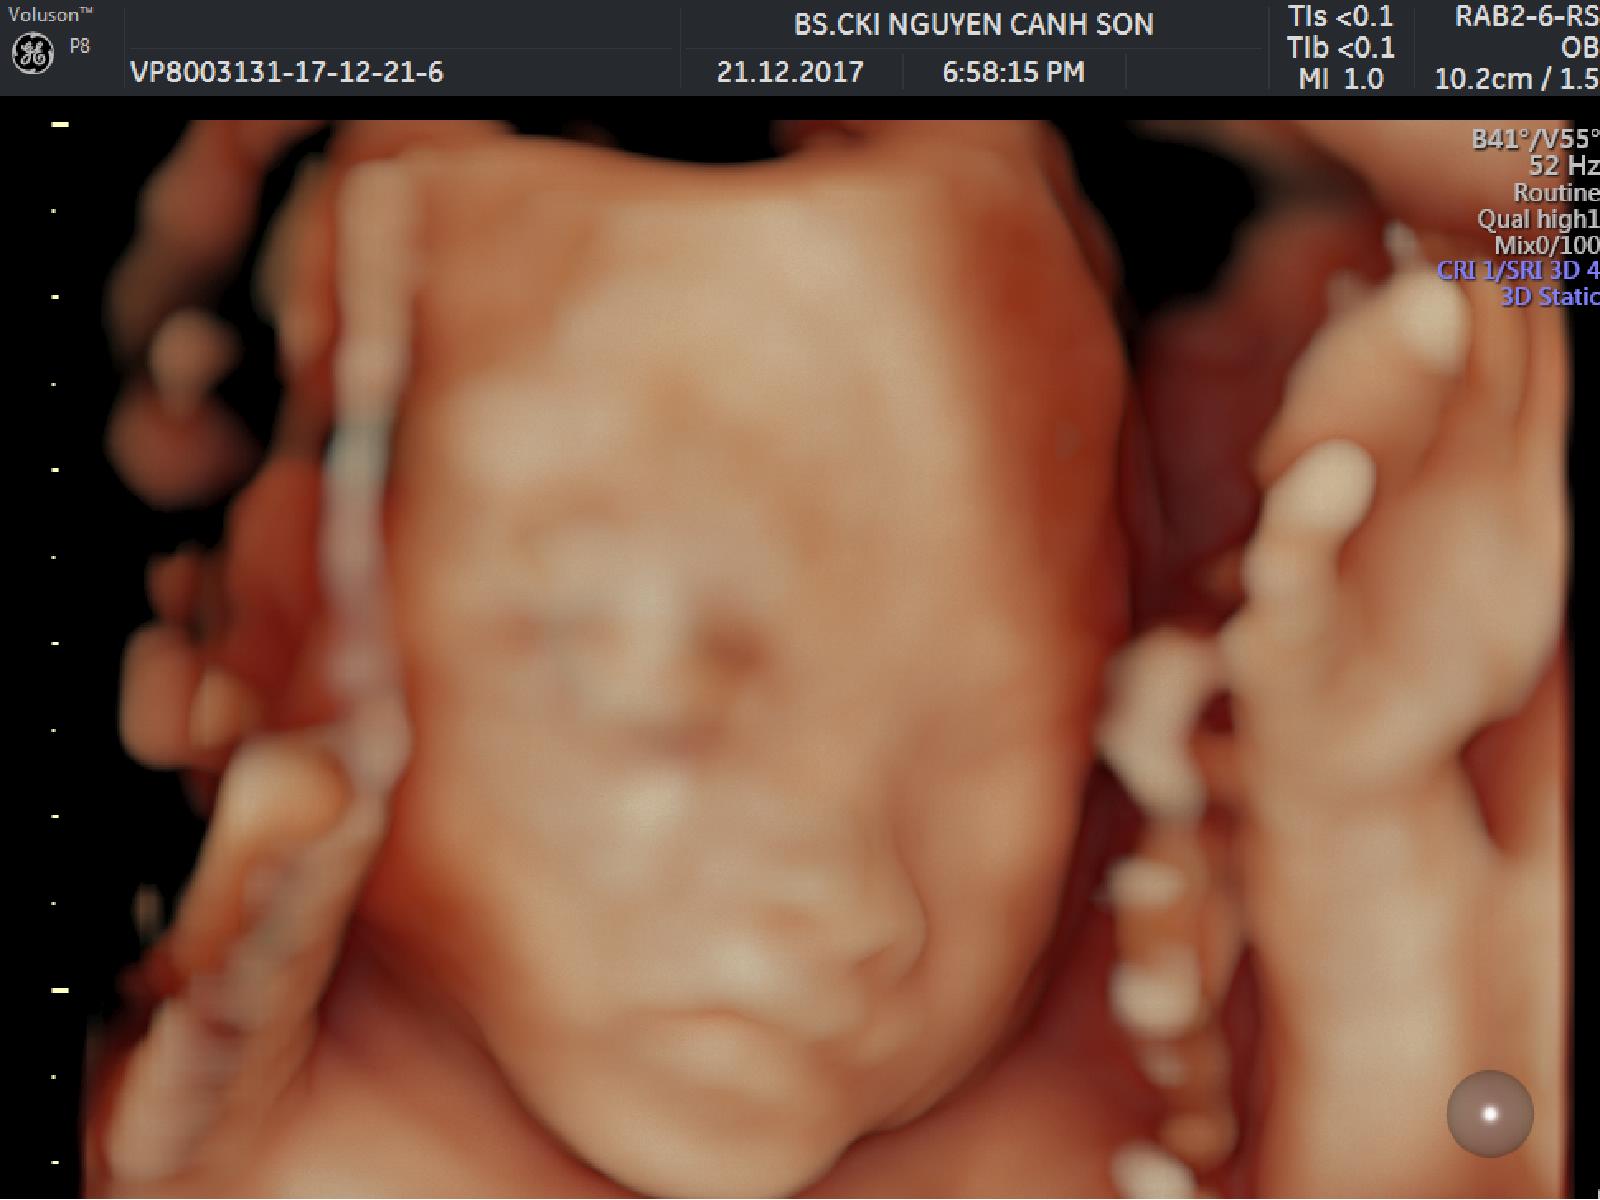

Siêu âm